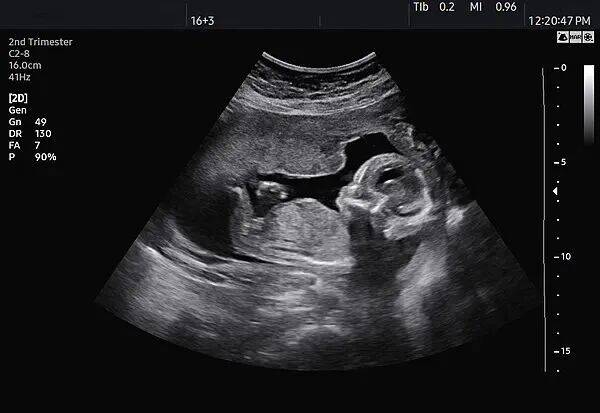

与此同时,该店使用B超机的行为也可能涉嫌违法。《关于严禁非法使用超声诊断仪开展“胎儿摄影”活动的通知》规定,根据《医疗器械分类目录》规定,超声诊断仪属于第二类、第三类医疗器械,适用范围为医疗机构临床诊断。 非医疗机构不得使用超声诊断仪。该店并非医疗机构,使用的超声诊断仪来源不明、质量不明,操作设备的工作人员是否有资质、操作是否规范同样不明,可能会对孕妇和胎儿的健康产生一定影响。